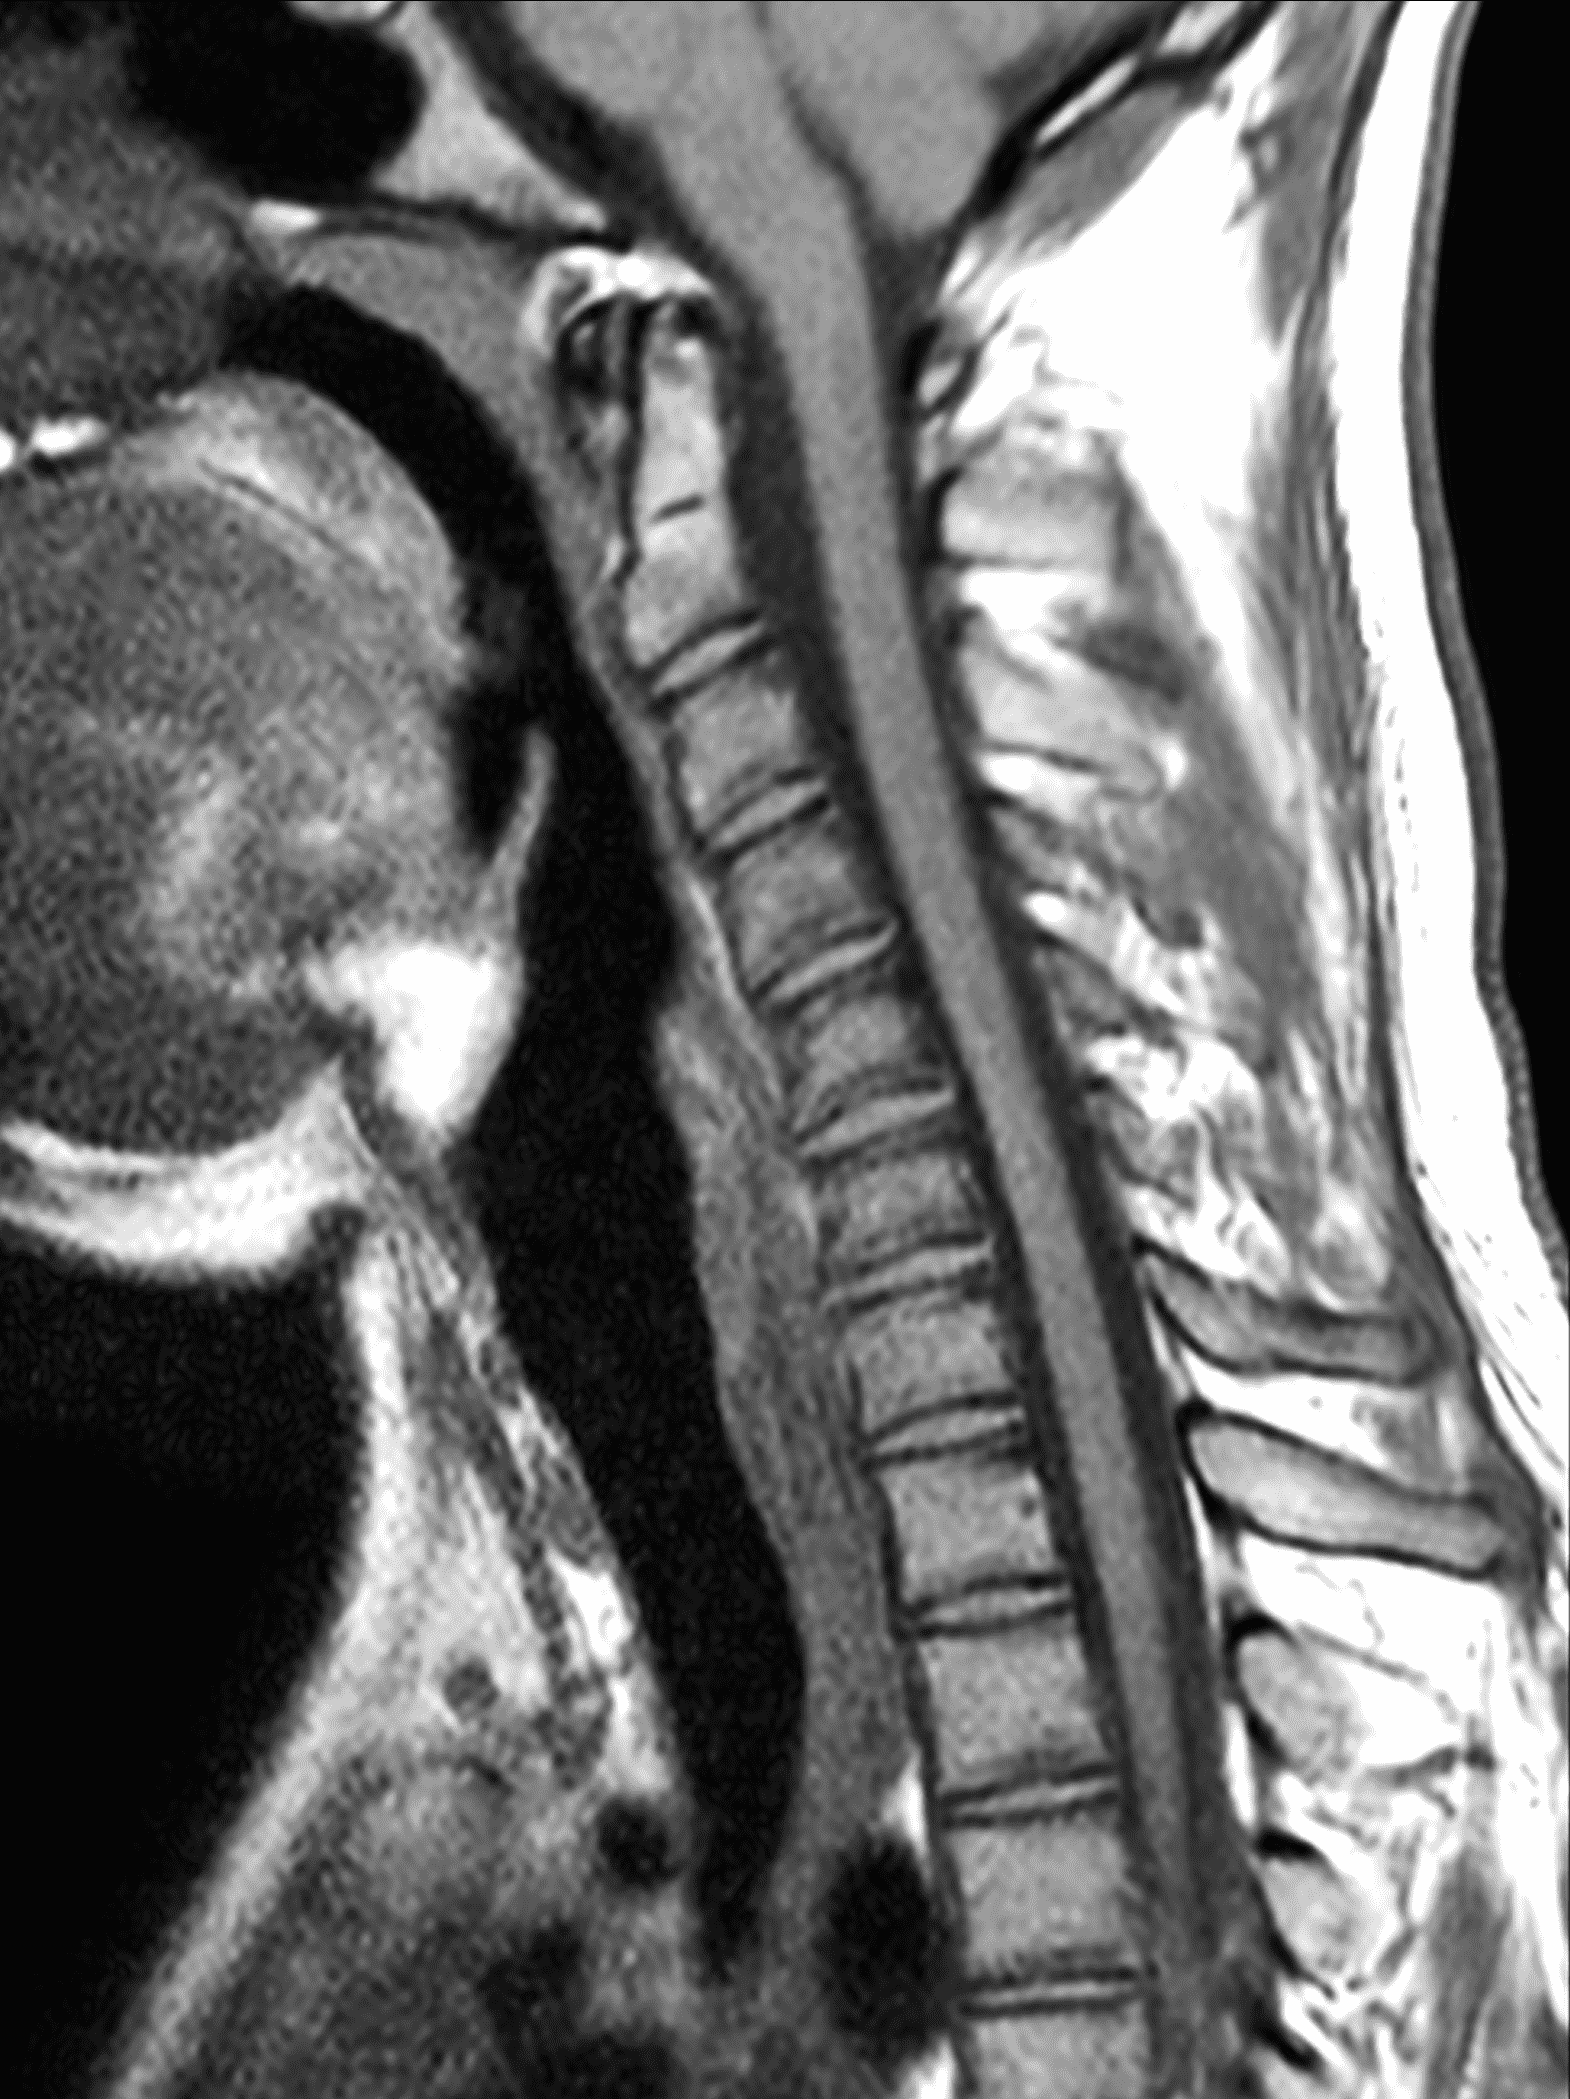

An 18 year old man presents with progressive motor wasting of right hand, progressive right hand weakness, claw-like deformity with flattening of the hand, and inability to straighten the ring and small fingers. He reports no numbness or pain. Sagittal T2-weighted (1A), sagittal T1-weighted (1B), sagittal STIR (1C), axial T2-weighted (1D), and axial T1-weighted (1E) images of the cervical spine obtained around the time of presentation are provided. What are the findings? What is your diagnosis?

Figure 2: Neutral images of the cervical spine. Sagittal (2A) T2-weighted, (2B) T1-weighted, and (2C) STIR images show mild kyphosis, an enlarged posterior epidural space with loss of attachment of the dura (red arrows), and cord atrophy at the C6 level (yellow arrow). Subtle cord hyperintensity on the water sensitive images at the C7 level (green arrows) likely represents gliosis. (2D) Axial T2-weighted image shows enlargement of the posterior epidural space, right greater than left (red arrows). (2E) Axial T1-weighted image shows an enlarged posterior epidural space (red arrows) and cord atrophy, more severe on the right (yellow arrow).